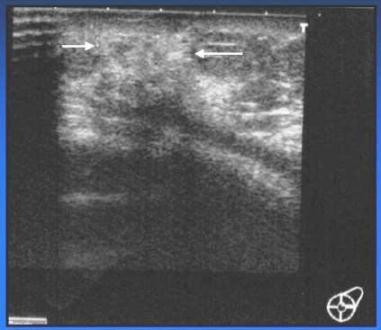

- UZ – vlevo uzlovitá heterogenní struktura žlázy s anechogenními tekutinovými porcemi, v axile bez lymfadenopatie

- UZ – heterogenní lehce hypoech. Ložisko s anechogen. Cystickými porcemi